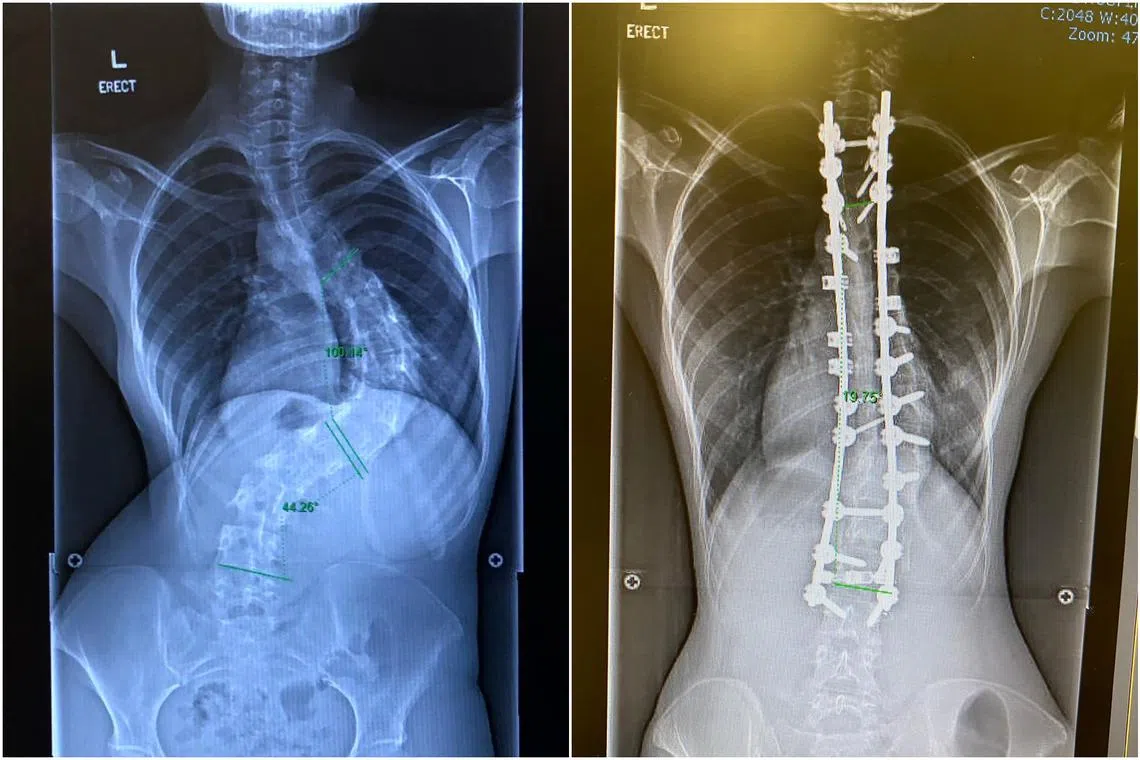

To correct severe scoliosis (left), Ms Natasha Ramli had to have two titanium rods and 20 screws implanted in her back (right).

“I suffered back pains, developed uneven hips and had trouble breathing. When the surgeon discovered how severe the curve was, I was told to go for surgery if I wanted a good quality life,” she said. She had two titanium rods and 20 screws implanted in her back.